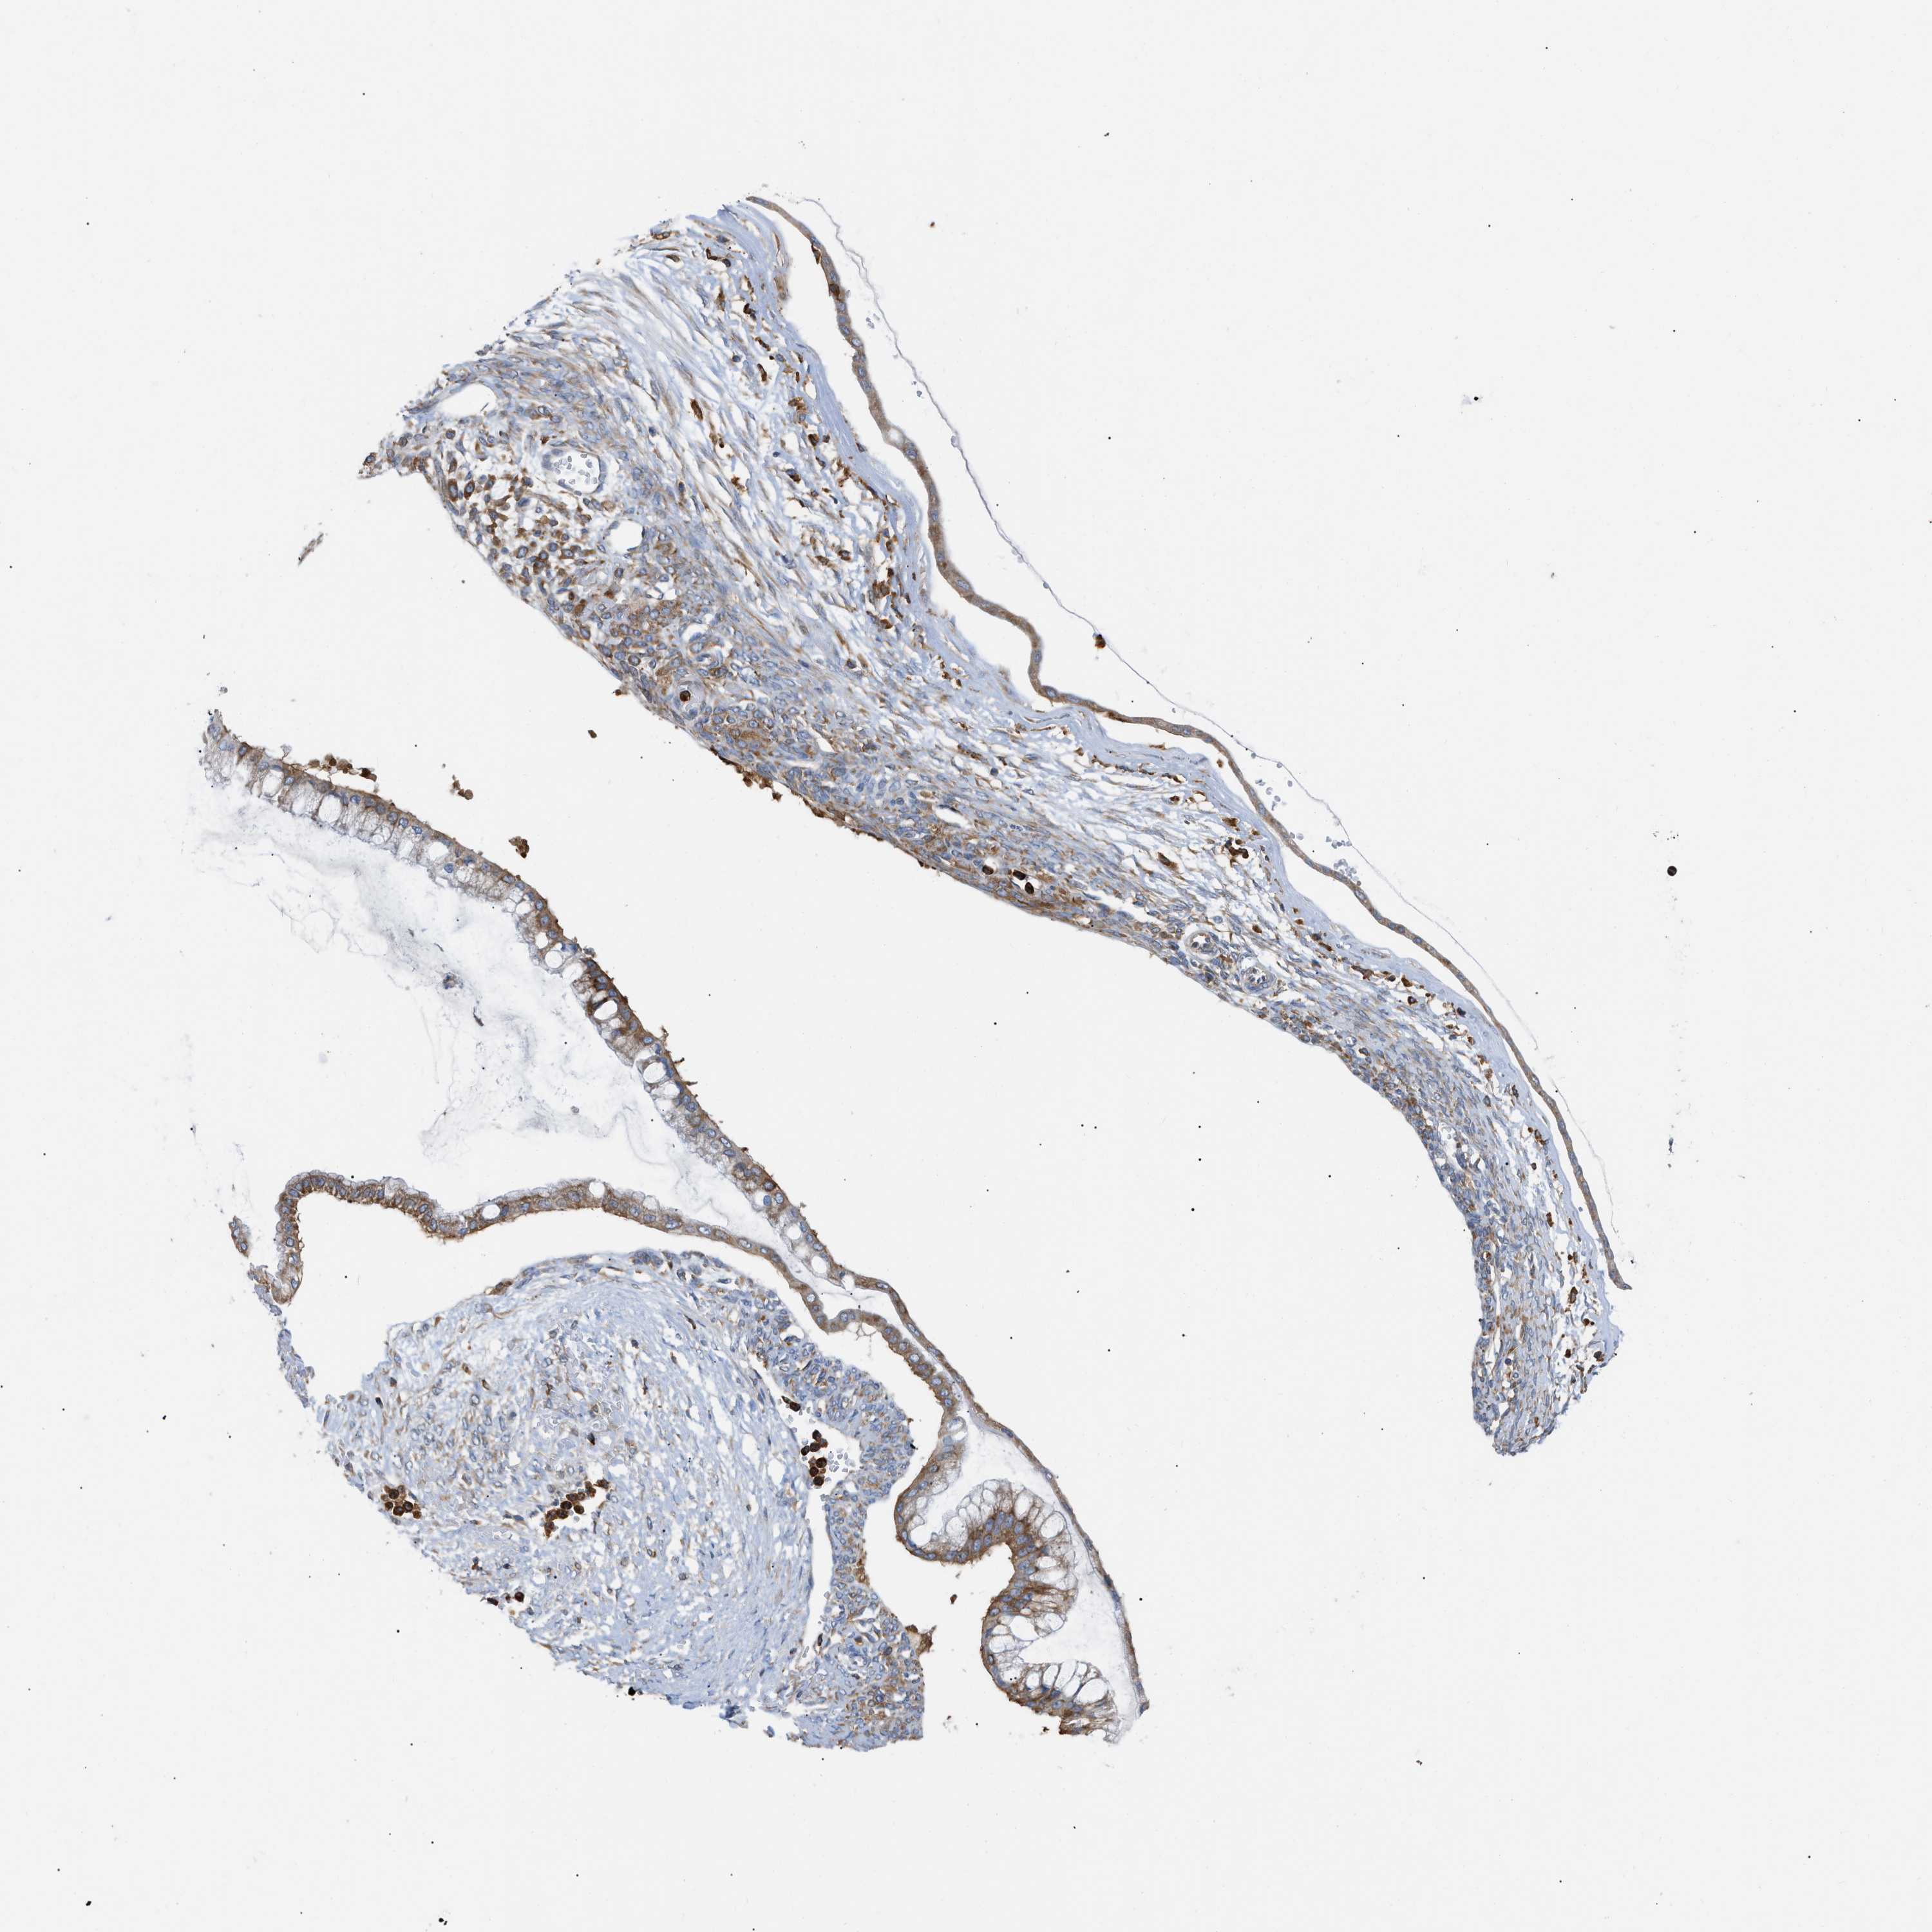

OVARIAN CANCER - Protein expressioni

A mouse-over function shows sample information and annotation data. Click on an image to view it in a full screen mode. Samples can be filtered based on level of antibody staining by selecting one or several of the following categories: high, medium, low and not detected. The assay and annotation is described here.

Note that samples used for immunohistochemistry by the Human Protein Atlas do not correspond to samples in the TCGA dataset.

Antibody stainingi

Antibody staining in the annotated cell types in the current human tissue is reported as not detected, low, medium, or high, based on conventional immunohistochemistry profiling in selected tissues. This score is based on the combination of the staining intensity and fraction of stained cells.

Each image is clickable and will lead to virtual microscopy that enables deeper exploration of all samples and also displays staining intensity scores, fraction scores and subcellular localization as well as patient and tissue information for each sample.

Antibody HPA016471

Staining

High

Medium

Low

Not detected

Intensity

Strong

Moderate

Weak

Negative

Quantity

>75%

75%-25%

<25%

None

Location

Nuclear

Cytoplasmic/membranous

Cytoplasmic/membranous,nuclear

Cystadenocarcinoma, serous, NOS

Carcinoma, endometroid

Cystadenocarcinoma, mucinous, NOS

Carcinoma, NOS